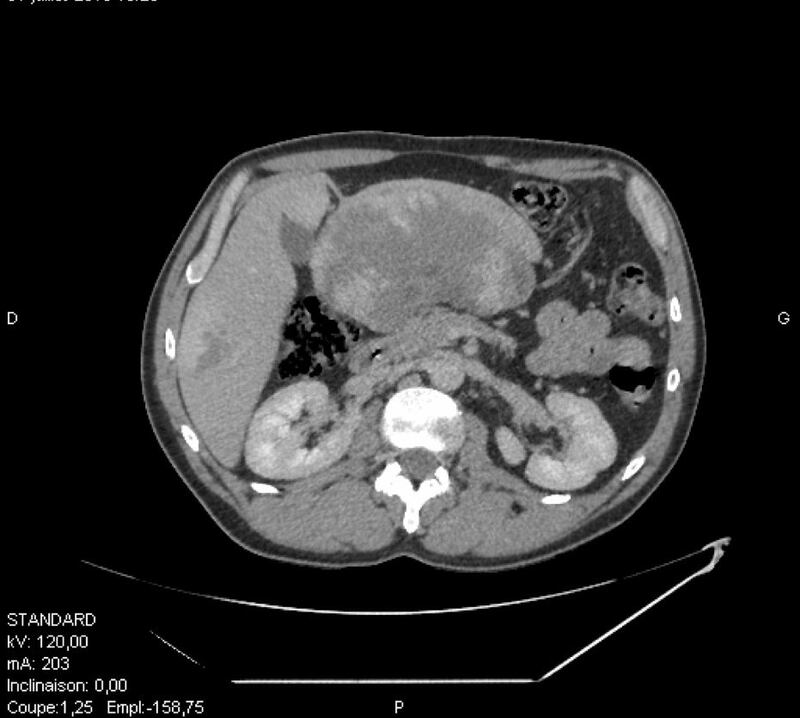

وكان المريض قد راجع المستشفى بعد تعرضه لآلام حادة في البطن في العمل قبل شهر واحد من حضوره، حيث كشف الفحص السريري عن كتلة كبيرة واضحة في البطن تحتل معظم المنطقة الشرسوفية الشريانية اليمنى “أعلى ويمين البطن”. كانت اختبارات الدم طبيعية تقريبا، وأظهر التصوير بالموجات الصوتية للبطن كتلة ضخمة غير متجانسة (18 × 10 سم) تقع في المنطقة الشرسوفية أمام البانكرياس وتتسب بضغط على الفص الأيسر للكبد باتجاه الأمام. وأظهر المسح المقطعي المحسّن للتجويف الحوضي والبطني وجود ورم نسيجي هائل أمام البانكرياس بقياس حوالي 20 × 9 × 16 سم.

وأضاف الدكتور : هنا أخذنا القرار بإجراء تصوير بالرنين المغناطيسي للكبد لتأتي النتائج لتظهر وجود العديد من الأورام الوعائية المنتشرة في جميع أنحاء الكبد بعد الحقن بصبغة تظهر التباين في الأورام. الورم الأكبر حجما هو ورم وعائي متشعب نشأ من الجزء الكبدي الثالث، مع تطور خارجي “التنبت” في المنطقة الشرسوفية يدفع البنكرياس إلى الوراء. أبعاد الورم 20 × 8 × 14 سم وهو يُعد الأضخم ضمن الحالات المسجلة عالمياً، كان هناك خطر بحصول التواء أو تمزق للورم يعقد من الحالة، ولذلك تم أخذ القرار بإجراء استئصال جراحي دون أخذ “خزعة” من الورم مسبقاً، وبالفعل قمنا بإجراء العملية الجراحية واستئصال الفص الأيسر للكبد المصاب دون أية آثار جانبية، وخرج المريض من المستشفى في اليوم الرابع بعد العملية الجراحية، حيث شارك في هذه العملية الجراحية فريق من ثلاثة جراحين متخصصين”.